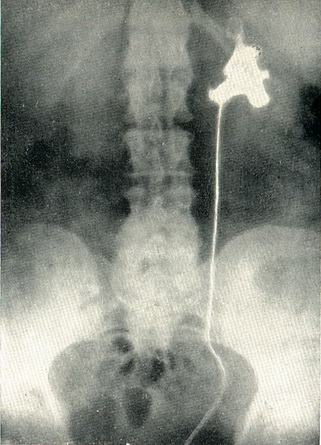

Рис 106. Пухлину миски лівої нирки. Дефект наповнення на ретроградної пиелограмме

Діагноз простий, коли при цистоскопії, виконаної з приводу гематурії, виявляється, що стирчить з гирла сечоводу ворсіна пухлини. Характерно поява крові з сечоводу при травмуванні пухлини кінчиком сечовідного катетера. Найбільш важливим методом діагностики є ретроградна пієлографія, при якій виявляється дефект наповнення ниркової миски, іноді з розширенням і деформацією її (рис. 106).